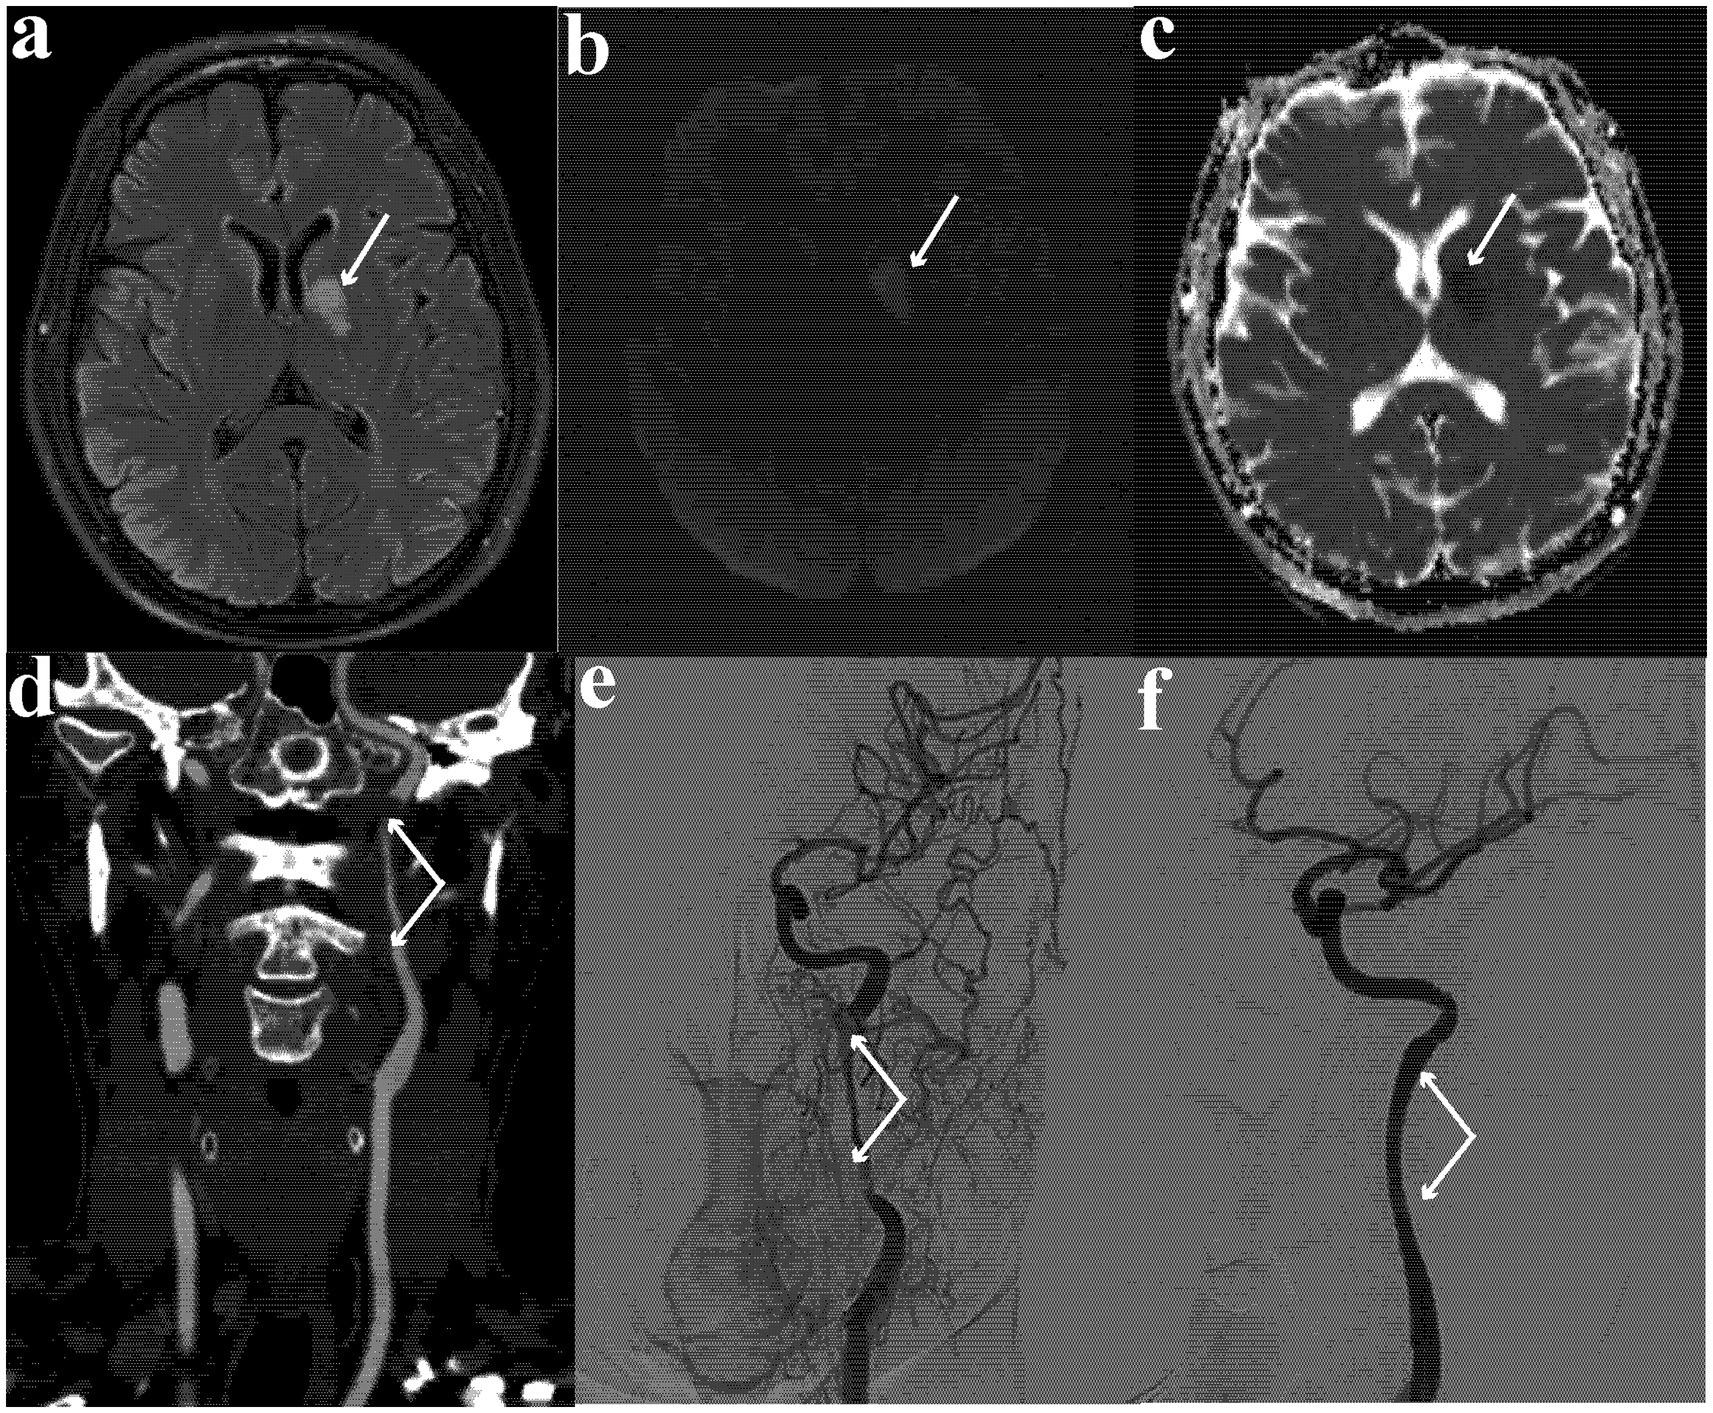

Brain magnetic resonance imaging showed an oval hyperintensity lesion at the left basal ganglia and inner capsule (in the territory of the left internal carotid artery) on fluid-attenuated inversion recovery (Figure 2a) and diffusion-weighted imaging (Figure 2b), and reduced apparent diffusion coefficient at the lesion (Figure 2c). Computed tomography angiography showed near-occlusion of the upper cervical segment of the left internal carotid artery (ICA) and wave-like tunica intima of proximal ICA (Figure 2d), confirmed as carotid dissection with severe stenosis on digital subtraction angiography (Figure 2e).

Figure 2

(a) Hyperintense oval lesion at left basal ganglia and inner capsule on fluid-attenuated inversion recovery image; (b) hyperintense oval lesion on diffusion-weighted imaging; (c) reduced apparent diffusion coefficient at the lesion; (d) near occlusion at the upper cervical segment of internal carotid artery and wave-like tunica intima of proximal carotid artery on computed tomography angiogram; (e) carotid dissection with severe stenosis on digital subtraction angiography; (f) repaired internal carotid artery and patent left ICA lumen.